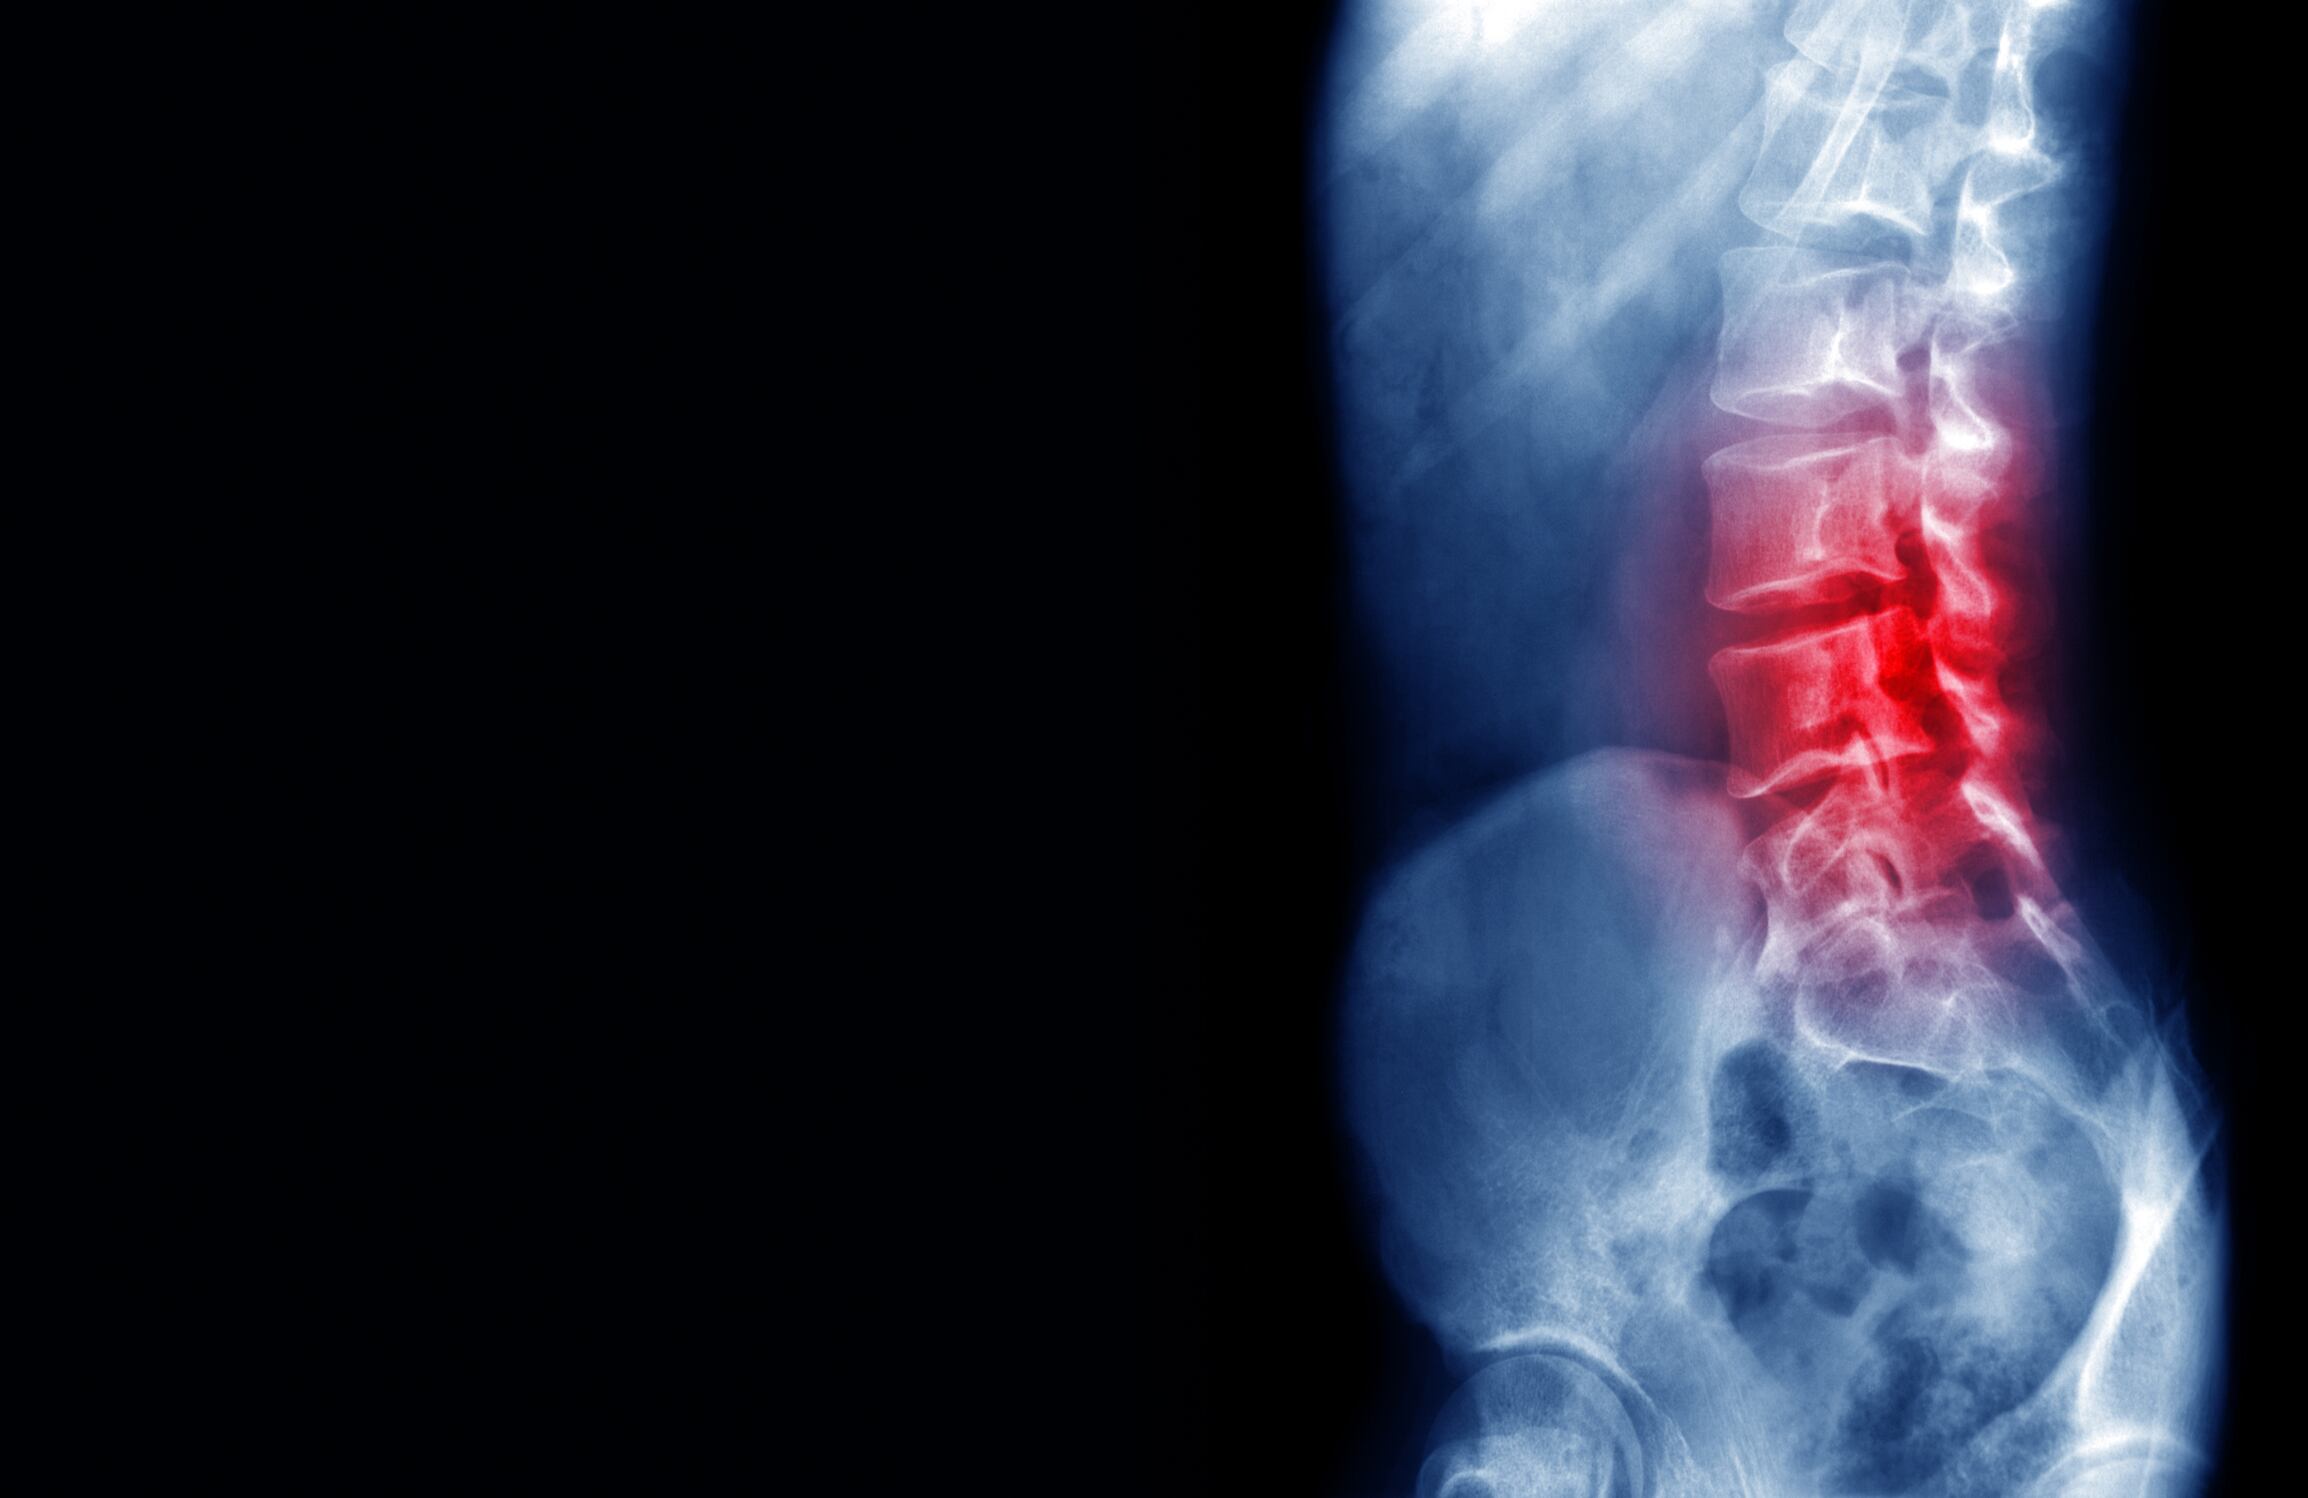

Dolor lumbar